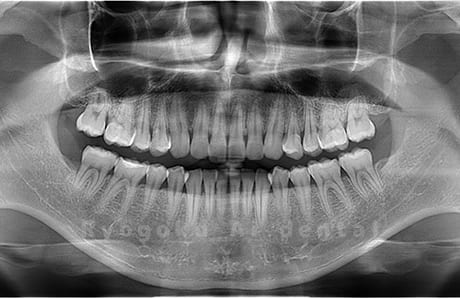

Case05

-

- 原因

- 下顎の親知らず2本

- 治療内容

- 下顎の親知らず2本を抜歯したケースです。

<リスク・副作用>

手術後は痛み、腫れ、痺れなどの副作用が生じる場合があります。